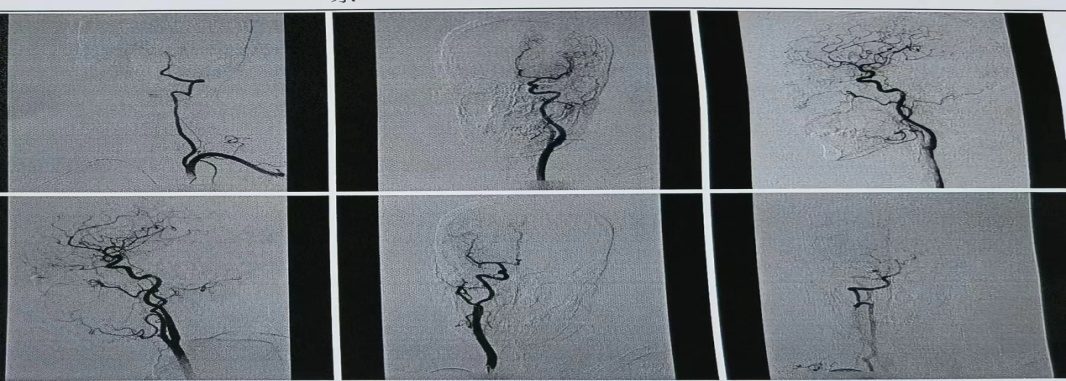

患者以肢体无力就诊,颅脑核磁提示颅内动脉多发节段性狭窄,明确诊断为多发脑梗死。王乐医师指导受援科室介入团队采取经“桡动脉全脑血管造影术”,明确患者脑血管狭窄情况。取得患者及家属充分知情同意后,手术用时不到1小时,过程顺利,患者生命体征平稳,术后即刻下床,活动自如。术后6小时拆除桡动脉压迫器,穿刺处无渗血渗液及硬结,搏动正常,患者无任何不适。

全脑血管造影术是评估脑血管的“金标准”。经桡动脉全脑血管造影术是近年来较先进的脑血管检查技术,为脑血管疾病的诊断和治疗提供重要依据。经桡动脉穿刺较传统经股动脉穿刺具有以下优势:一、穿刺点损伤小,术中及术后并发症少,术后护理方便安全;二、术后患者即刻下床活动,舒适度好,易于接受,尤其对于肢体瘫痪或高龄的老年人;三、术后下肢不需长时间制动,避了下肢深静脉血栓的形成,不影响患者康复锻炼及其他治疗。